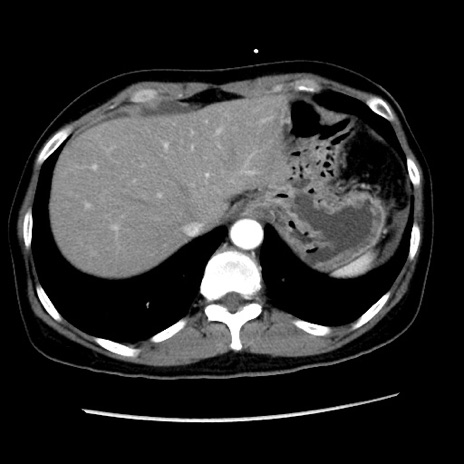

冠状断像

【症例】 50歳代女性

【主訴】 腹痛

【現病歴】前日生レバーを食べた。今朝に排便あり。 昼前に突然発症の腹痛を生じ、当院救急外来を受診した。

【身体所見】 意識清明、腹部:平坦、軟、下腹部やや左を中心に圧痛・反跳痛あり、筋性防御あり

【データ】WBC 7800、CRP 0.07